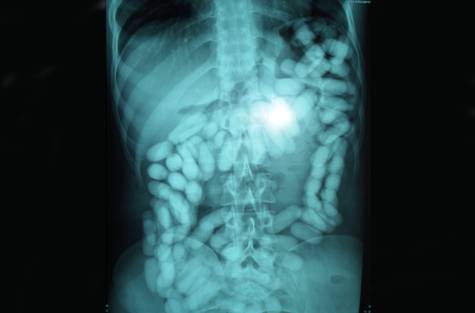

Het gaat om twee mannen en een vrouw die elk honderd cocaïnebolletjes hadden geslikt. Met hun Amerikaanse nationaliteit hoopten zij door de marechaussee in Nederland te kunnen glippen die de aandacht vooral vestigt op vluchten uit Suriname en de Antillen…[+]